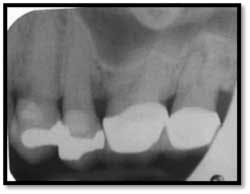

Pockets 4-9mm Class ll furcation involvement in both molars, possible endo abscess #3, (tooth is asymptomatic)

Pockets 4-7mm Possible periapical abscess #15

A full set of radiographs taken 13 months post therapy show bone fill in the deepest pockets, with generalized pocket reductions of up to 7mm.

#3 was referred for endodontic evaluation.

#’s 15 and 18 show no signs of endodontic involvement, #15 tests vital.